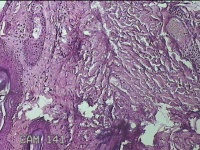

左侧会阴部皮下结节

性别

女

年龄

45岁

临床诊断

皮下结节

一般病史

发现左侧会阴部皮下结节2年余,伴近日局部隐痛不适。

标本名称

大体所见

灰白暗红色结节0.8x0.7x0.3cm一个,表面糜烂。

图2